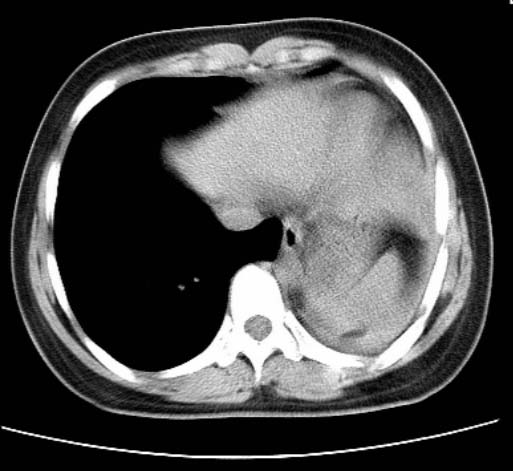

标题: CT25648:求教:是肺发育不全还是结核?

女  20岁。一月前咳血,诊“肺结核”抗痨治疗一月后,咳血停止,现复查。病人精神好。前后ct片对比未见明显变化。既往体检“正常”

1)考虑左肺结核并肺不张、支气管扩张。2)纵隔疝。

考虑左肺结核,左肺毁损,纵膈左偏,既往体检正常不可靠,tb一个月也不会这个样子的,有钙化,应该病程较长,冰冻三尺非一日之寒!

考虑左肺结核,左肺毁损,纵膈左偏,既往体检正常不可靠,tb一个月也不会这个样子的,有钙化,应该病程较长,冰冻三尺非一日之寒